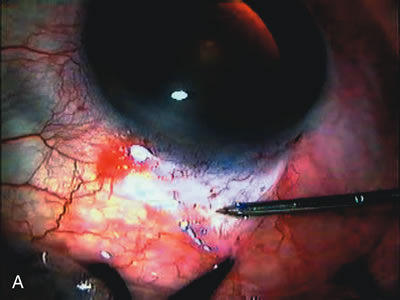

Fig. 1. The anatomic advantage of small incision cataract surgery for the glaucoma patient. A. Long-term bleb function with a large cataract incision is difficult to achieve with either ECCE-trabeculectomy or trabeculectomy followed later by ECCE. This bleb failed to form sufficiently when combined with large incision ECCE. The inflammation, bleeding, and long-term wound healing with stimulation of fibroblasts associated with this technique are more likely to cause bleb failure. In addition, the increased iris manipulation necessary to deliver the nucleus and subsequent iris repair adds to the long-term breakdown of the blood aqueous barrier. B and C. Two-site phacotrabeculectomy has the advantage of small incision cataract surgery combined with separate site trabeculectomy. The incision size is one third the size of the standard ECCE. The inflammation is less severe, and cataract wound healing is confined to the temporal area. Visual rehabilitation with phacoemulsification and foldable IOL is much faster. Phacoemulsification allows successful lens extraction even in the unfriendly environment of a smaller pupil compared with ECCE. The trabeculectomy is performed in an entirely different site, well away from the wound healing associated with temporal phacoemulsification. The likelihood of this filter functioning long-term is greater than with ECCE-trabeculectomy. D. The surgeon also has the option of single-site phacotrabeculectomy with foldable IOL. Both the lens extraction and trabeculectomy are performed through one small 3.5-mm limbal incision.

Fig. 2. Wound modulation and revision. A. MMC decreases the likelihood of bleb failure in high-risk eyes undergoing combined cataract and glaucoma surgery. Overusage of this potent cytotoxic drug should be avoided owing to a myriad of problems related to the formation of an avascular bleb. B. Office-based laser revision of the operative wound allows for increased postoperative flexibility with less complications. The correct number and tension of scleral flap sutures allows the surgeon to strive for a safe immediate postoperative IOP range. When fibrosis occurs at approximately 1 week, suturelysis or release of sutures increases filtration while avoiding unwanted hypotony.